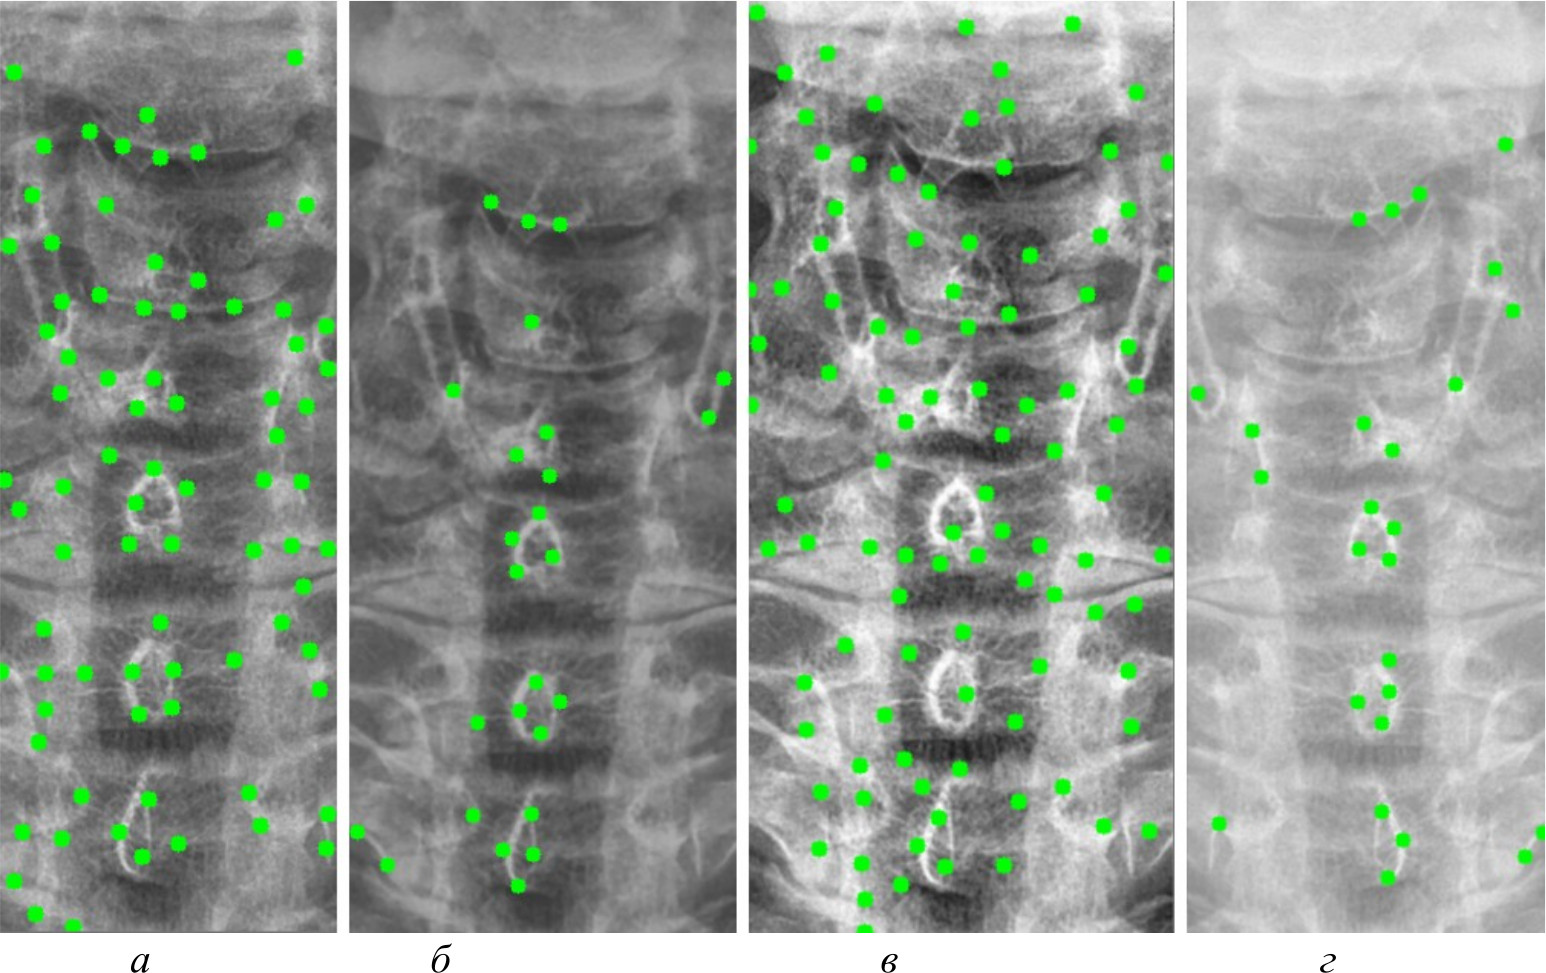

На рис. 4, 5 и 6 представлены результаты работы детектора Харриса, алгоритма Shi-Tomasi и SIFT при различных методах предварительной обработки изображений.

Рис. 4. Результаты работы детектора Harris на изображении, полученном при помощи специализированного программного обеспечения (а); результаты работы детектора Harris при методе адаптивной эквализации гистограммы (б); результаты работы детектора Harris при методе стандартной эквализации гистограммы (в); результаты работы детектора Harris при методе гамма-коррекции (г)

Рис. 5. Результаты работы алгоритма Shi-Tomasi на изображении, полученном при помощи специализированного программного обеспечения (а); результаты работы алгоритма Shi-Tomasi при методе базового отображения в Python (б); результаты работы алгоритма Shi-Tomasi при методе базового отображения Python с применением медианного фильтра (в); результаты работы алгоритма Shi-Tomasi при методе адаптивной эквализации гистограммы (г); результаты работы алгоритма Shi-Tomasi при методе стандартной эквализации гистограммы (д); результаты работы алгоритма Shi-Tomasi при методе гамма-коррекции (е)

Рис. 6. Результаты работы алгоритма SIFT на изображении, полученном при помощи специализированного программного обеспечения (а); результаты работы алгоритма SIFT при методе адаптивной эквализации гистограммы (б); результаты работы алгоритма SIFT при методе стандартной эквализации гистограммы (в)

После получения всех карт анатомических ориентиров составлена таблица и проведен сравнительный анализ. В таблице представлены данные сравнительного анализа методов предварительной обработки и алгоритмов распознавания анатомических ориентиров. В ней представлены следующие данные:

Метод | Принцип | Количество анатомических ориентиров (кластеров) и распределение по ним | Точность | Точность до обработки | ||

Harris | Shi-Tomasi | SIFT | ||||

Программа Dicom Image Viewer (эталон) | PNG-картинка полученная, специализированным программным обеспечением | 78 кластеров 6: 8, 15, 13, 14, 15, 13 | 80 кластеров 6: 8, 15, 15, 13, 14, 16 | 40 кластеров 4: 9, 15, 11, 6 | Harris – 87 %, Shi-Tomasi – 90 %, SIFT – 78 % | Harris – 65 %, Shi-Tomasi – 68 %, SIFT – 54 % |

Базовое отображение Python (Pillow) | Отображение при помощи библиотеки Pillow в Python | Не нашел | 80 Кластеров 6: 10, 10, 17, 15, 13, 15 | Не нашел | Shi-Tomasi – 45 % | Shi-Tomasi – 25 % |

Медианный фильтр | Отображение при помощи библиотеки Pillow в Python с применением фильтра Гаусса и медианного фильтра | Не нашел | 80 Кластеров 6: 8, 15, 11, 17, 14, 15 | Не нашел | Shi-Tomasi – 35 % | Shi-Tomasi – 22 % |

Адаптивная эквализация | Разбитие снимка на небольшие области и контрастирование каждой из них с применением фильтра Гаусса и медианного фильтра | 26 кластеров 6: 3, 1, 6, 4, 5, 7 | 80 кластеров 6: 4, 12, 17, 14, 12, 21 | 38 кластеров 6: 1, 4, 9, 10, 11, 3 | Harris – 77 %, Shi-Tomasi – 82 %, SIFT – 74 % | Harris – 65 %, Shi-Tomasi – 71 %, SIFT – 62 % |

Стандратная эквализация | Перераспределение значения пикселей для их равномерного распределения по диапазону. Данный метод выявляет более мелкие детали на изображении | 50 кластеров 6: 6, 8, 10, 8, 5, 10 | 80 кластеров 6: 8, 16, 16, 14, 10, 16 | 37 кластеров 6: 4, 8, 8, 9, 5, 3 | Harris – 91 %, Shi-Tomasi – 95 %, SIFT – 87 % | Harris – 74 %, Shi-Tomasi – 78 %, SIFT – 71 % |

Гамма-корректировка | Отображение при помощи библиотеки Pillow в Python с применением фильтра гамма-коррекции | 26 кластеров 6: 4, 2, 6, 4, 4, 6 | 80 Кластеров 6: 8, 15, 17, 12, 12, 16 | Не нашел | Harris – 55 %, Shi-Tomasi – 65 % | Harris – 38 %, Shi-Tomasi – 47 % |

Максимальное количество кластеров, которое может быть выделено, равно 6, так как на рентгеновских снимках выделялась часть спины, включающая 6 позвонков. Некоторые методы выделяют меньше кластеров, в то время как другие – больше; кроме того, часть методов не смогла распознать ключевые анатомические ориентиры вовсе. Это связано с особенностями алгоритмов и качеством предварительной обработки изображений.

Из данных таблицы видно, что наилучшим алгоритмом распознавания анатомических ориентиров является алгоритм Shi-Tomasi. Он распознал максимальное количество анатомических ориентиров вне зависимости от качества изображения, с которым работал, в то время как детектор Harris и алгоритм SIFT не смогли их распознать на изображениях, полученных при помощи базового отображения библиотекой Pillow, а также при применении медианного фильтра. Также алгоритм SIFT не смог найти ориентиры на изображении, полученном при гамма-коррекции.

Проанализировав все методы предварительной обработки и то, как алгоритмы смогли распознать ключевые анатомические ориентиры на них, можно сделать несколько выводов. Наилучшим методом оказалась стандартная эквализация изображений, при которой алгоритм Shi-Tomasi распознавал анатомические ориентиры с точностью около 95 %. Использование специализированного программного обеспечения также показало неплохие результаты, но немного уступало стандартной эквализации по точности распознавания – около 90 %. Остальные методы, такие как применение фильтров или гамма-коррекция, показали более низкую точность, в диапазоне от 35 до 75 %. В свою очередь, применение любого метода предварительной обработки повышало точность распознавания ключевых анатомических ориентиров на 15–25 %. В итоге наиболее предпочтительными методами оказались стандартная эквализация и специализированное программное обеспечение.